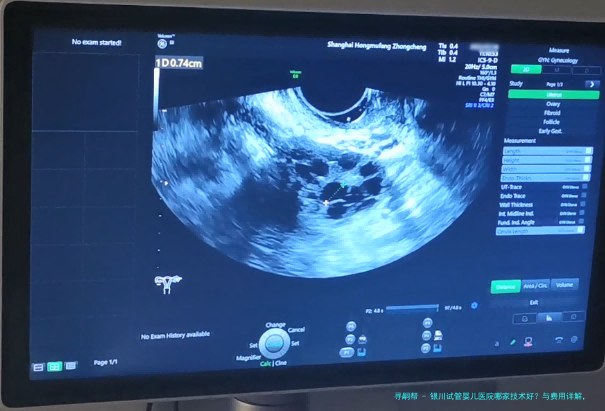

孕期早期监测(B超等)1500//td>8001100900-1300